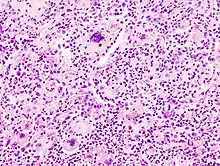

Kriterien der Malignität

- Histologisch: Nekrosen, Kapillarisierung (Neoangiogenese), Aufhebung der normalen Histologie.

- Zytologisch: Polymorphie, basophiles Cytoplasma, erhöhte Kern/Plasmarelation

- Nukleär: Polymorphie, Polychromasie, Hyperchromasie, Aneuploidie, (vergrößerte) Nukleolen, vermehrt Mitosen, atypische Mitosen, erhöhter Proliferationsindex (Ki-67 = MIB-1).